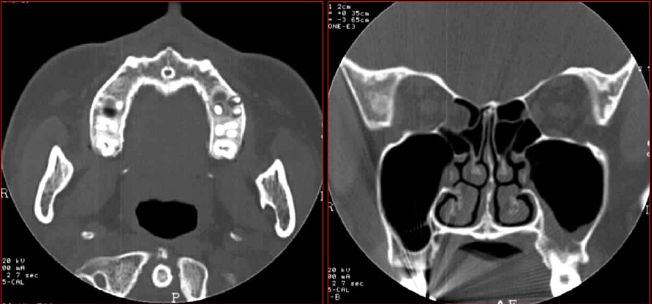

牙源性鼻窦炎